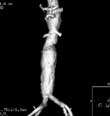

These images are acquired in a conventional CT scanner using a technology that synchronizes the acquisition of the images with the injection of an intravenous contrast material in such a way that the bolus of contrast is visualized while it transits the arteries of the specific organ or segment being studied. Then the images are processed to allow three-dimensional reconstructions for further manipulation and/or therapeutic planning.

Different to regular angiograms, CTA does not require selective catheterization of the arteries. In other words no punctures of arteries are necessary. In addition to the visualization of arteries and their branches, CTA renders depictions of the bone structures and to some extent other soft tissues. This feature is very important in the evaluation of conditions such as carotid stenosis, intra and extracranial atherosclerosis, and aneurysms.

The high quality of these images and elevated speed of acquisition allow the examination of large sections of the body in just few seconds with a great amount of detail. This degree of detail makes CTA a very valuable tool for the planning of both surgical and minimally invasive vascular procedures and for the diagnosis and follow-up of wide spectrum of cerebrovascular diseases.